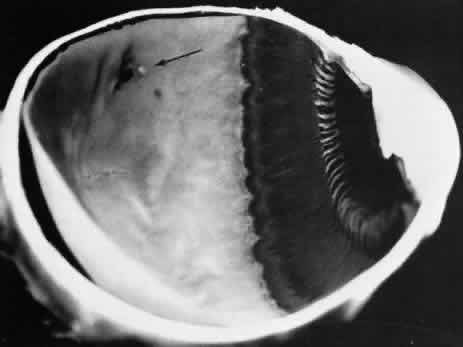

NONCYSTIC RETINAL TUFT

A noncystic retinal tuft is a short, thin internal projection of retinal tissue that usually occurs in clustersand is almost invariably located within the vitreous base. From the vitreous attachment at the apex, the tuft extends to a base that is less than 0.1 mm in diameter and unassociated with cystic retinal degeneration (Fig. 36). Histologically, a noncystic tuft is composed of altered retinal cells and proliferated glial tissue (Fig. 37).27,34 Noncystic retinal tufts are not present at birth. They are present in 72% of adult patients, are bilateral in 50% of affected individuals, and thus are present in 59% of adult eyes (see Table3). Tufts occur in all sectors, but they are most common in the inferior nasal quadrant and are almost always located in the anterior portion of the peripheral retina corresponding to the vitreous base.

Fig. 36. Noncystic retinal tufts: cluster of small surface nodules of retina within vitreous base. Surrounding retina shows nonspecific degeneration and pigment dispersion. (× 20.)

Fig. 37. Microscopic features of the lesion seen in Figure 36. Entire retina within vitreous base shows nonspecific degeneration with gliosis. Centrally, the surface is elevated and shows a plaque of dense-staining glial cells. Retinal pigment epithelium also shows irregular thinning and pigment clumping, characteristically found within vitreous base. (Hematoxylin-eosin stain; × 500.)

On clinical examination, these tufts are commonly observed as small, pointed retinal projections within the area of the vitreous base. In later life, degenerative changes within the tufts may cause the tips of the tufts to break off, producing small spherical fragments that float in the vitreous adjacent to the base. These tufts are not associated with full-thickness retinal breaks and can be considered to be innocuous.